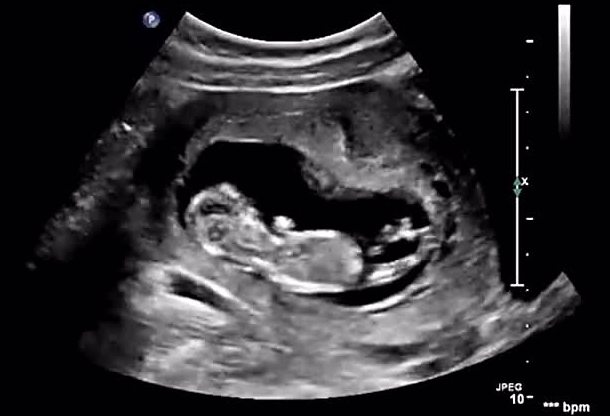

孕16周最明显的女性宝宝b超图片该怎么看?

问题描述: 我现在已经怀孕16周了,现在宝宝外观已经发育的比较完全了,这一胎我们全家都很希望是一个女儿,听其他人说通过B超检查报告单上的图片可以看出是否是女儿,但是我自己拿着看了半天还是没看懂,所以想请教一下如果是女儿那么最明显的地方该怎么看呢?

最明显的女性宝宝b超图看宝宝双腿间生殖器官区域。如果是女性宝宝,重点观察她的生殖器官区域,由于女性胎儿的尿道、阴道和肛门是从前往后依次排列的,这种“平行线”状的结构在B超图像上较为明显,一般可以看到三条平行线。

尽管在孕16周可以通过B超图像辨认出一些是男是女的特征,但需要注意的是,并不是所有的B超图像都能清晰显示出来。图像质量受到多种因素的影响,包括设备性能、患者因素、操作者的经验等。具体如下: